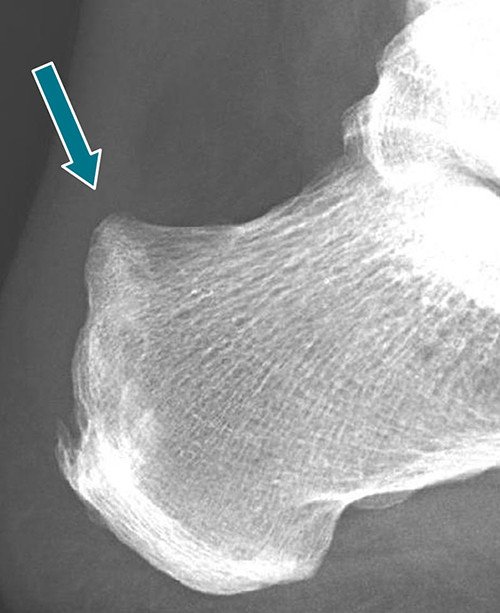

Auf dem konventionellen Röntgenbild kann eine sogenannte Haglund-Fersenkonfiguration nachgewiesen werden (Abb. 1).